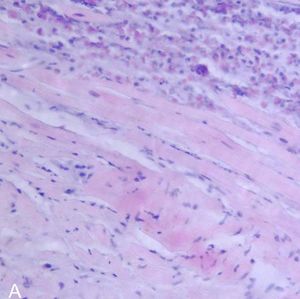

صورة نسيجية لالتهاب فيروسي لعضلة القلب في عملية تشريح لمريض مصاب بالمرض. | |

يتم كشف التهاب العضلة القلبية عن طريق استخدام مخطط القلب الكهربائي(ECG)،وهناك أيضاً علامات للالتهاب من عدم انتظام تركيز الكرياتين (creatine)، والتروبونين (troponin). ويمكن كشفها أيضاً عن طريق عمل القسطرة، بحيث يتم عمل فحص لنسيج القلب، بحيث يتم أخذ عينة صغيرة من النسيج الداخلي والخارجي للقلب، ويتم فحصها من قبل مختص أمراض من خلال مجهر ضوئي. حديثاً، أصبح بالإمكان الكشف من خلال استخدام جهاز الأشعة المغناطيسية لمنطقة القلب (cMRI: Cardiac Magnetic Resonance Image)، وقد تبين أنها طريقة نافعة.